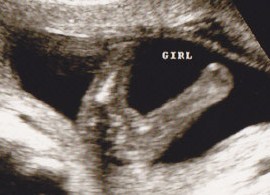

Girl!!??? :) I am in disbelief..... we wanted a girl.... I am nervous about getting my heart set...

Thank you sooooo much!! :HH: :HH: Can I tell people the baby's gender? It's super clear right? :)